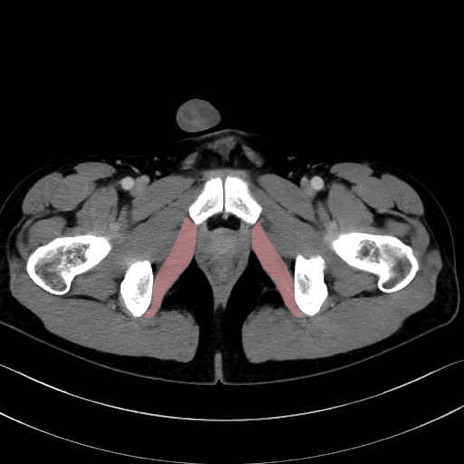

内閉鎖筋 (Obturator internus)